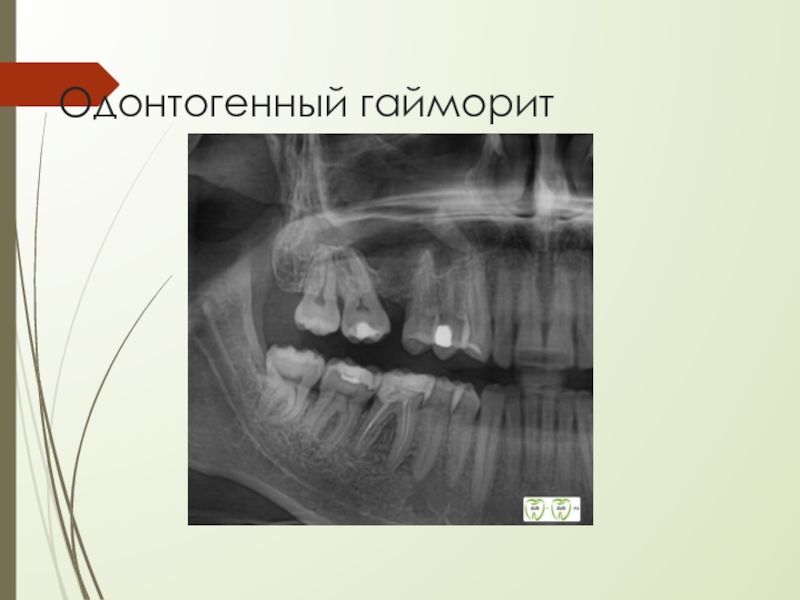

Слайд 44Одонтогенный гайморит

Одонтогенный гайморит